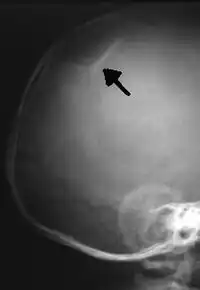

The material factual allegations of the amended complaint are as follows. Plaintiff was born on May 14, 1970. On repeated occasions during the first year of her life she was severely beaten by her mother and the latter's common law husband, one Reyes. On April 26, 1971, when the plaintiff was eleven months old, her mother took her to the San Jose Hospital for examination, diagnosis, and treatment. The attending physician was defendant Dr. Flood, acting on his own behalf and as agent of the defendant San Jose Hospital. At the time, the plaintiff was suffering from a comminuted spiral fracture of the right tibia and fibula, which gave the appearance of having been caused by a twisting force. Plaintiff's mother had no explanation for this injury. Plaintiff had bruises over her entire body. In addition, she had a non-depressed linear skull fracture which was then in the process of healing. Plaintiff demonstrated fear and apprehension when approached. Inasmuch as all plaintiff's injuries gave the appearance of having been intentionally inflicted by other persons, she exhibited the medical condition known as the battered child syndrome.

Landeros presented to the emergency room with a spiral fracture of the tibia, among other injuries.

X-ray image of a depressed skull fracture in an infant. This injury is typical of child abuse cases.